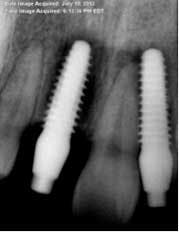

Implant sites were curetted well, then disinfected with Chloramine-T saturated gauze, followed by irrigation with 2% chlorhexidine and water. Bone grafting was not deemed necessary. Both implants No. 8 and No. 10 were replaced with TRX-OP 4.5 x 13 mm (Fig. 5). The patient was informed that because implants placed into previously failed sites have a lower success rate, absolute adherence to postoperative instructions was critical to any chance of success (4). Instructions were once again given to follow dietary restrictions and take the antibiotics as prescribed. The patient was seen six weeks postoperatively (Fig. 6) and set to have the final prosthesis inserted six months post-reimplantation.Fig. 5: No. 8 and No. 10 — implants replaced by 4.5 x 13 mm and retemporized.